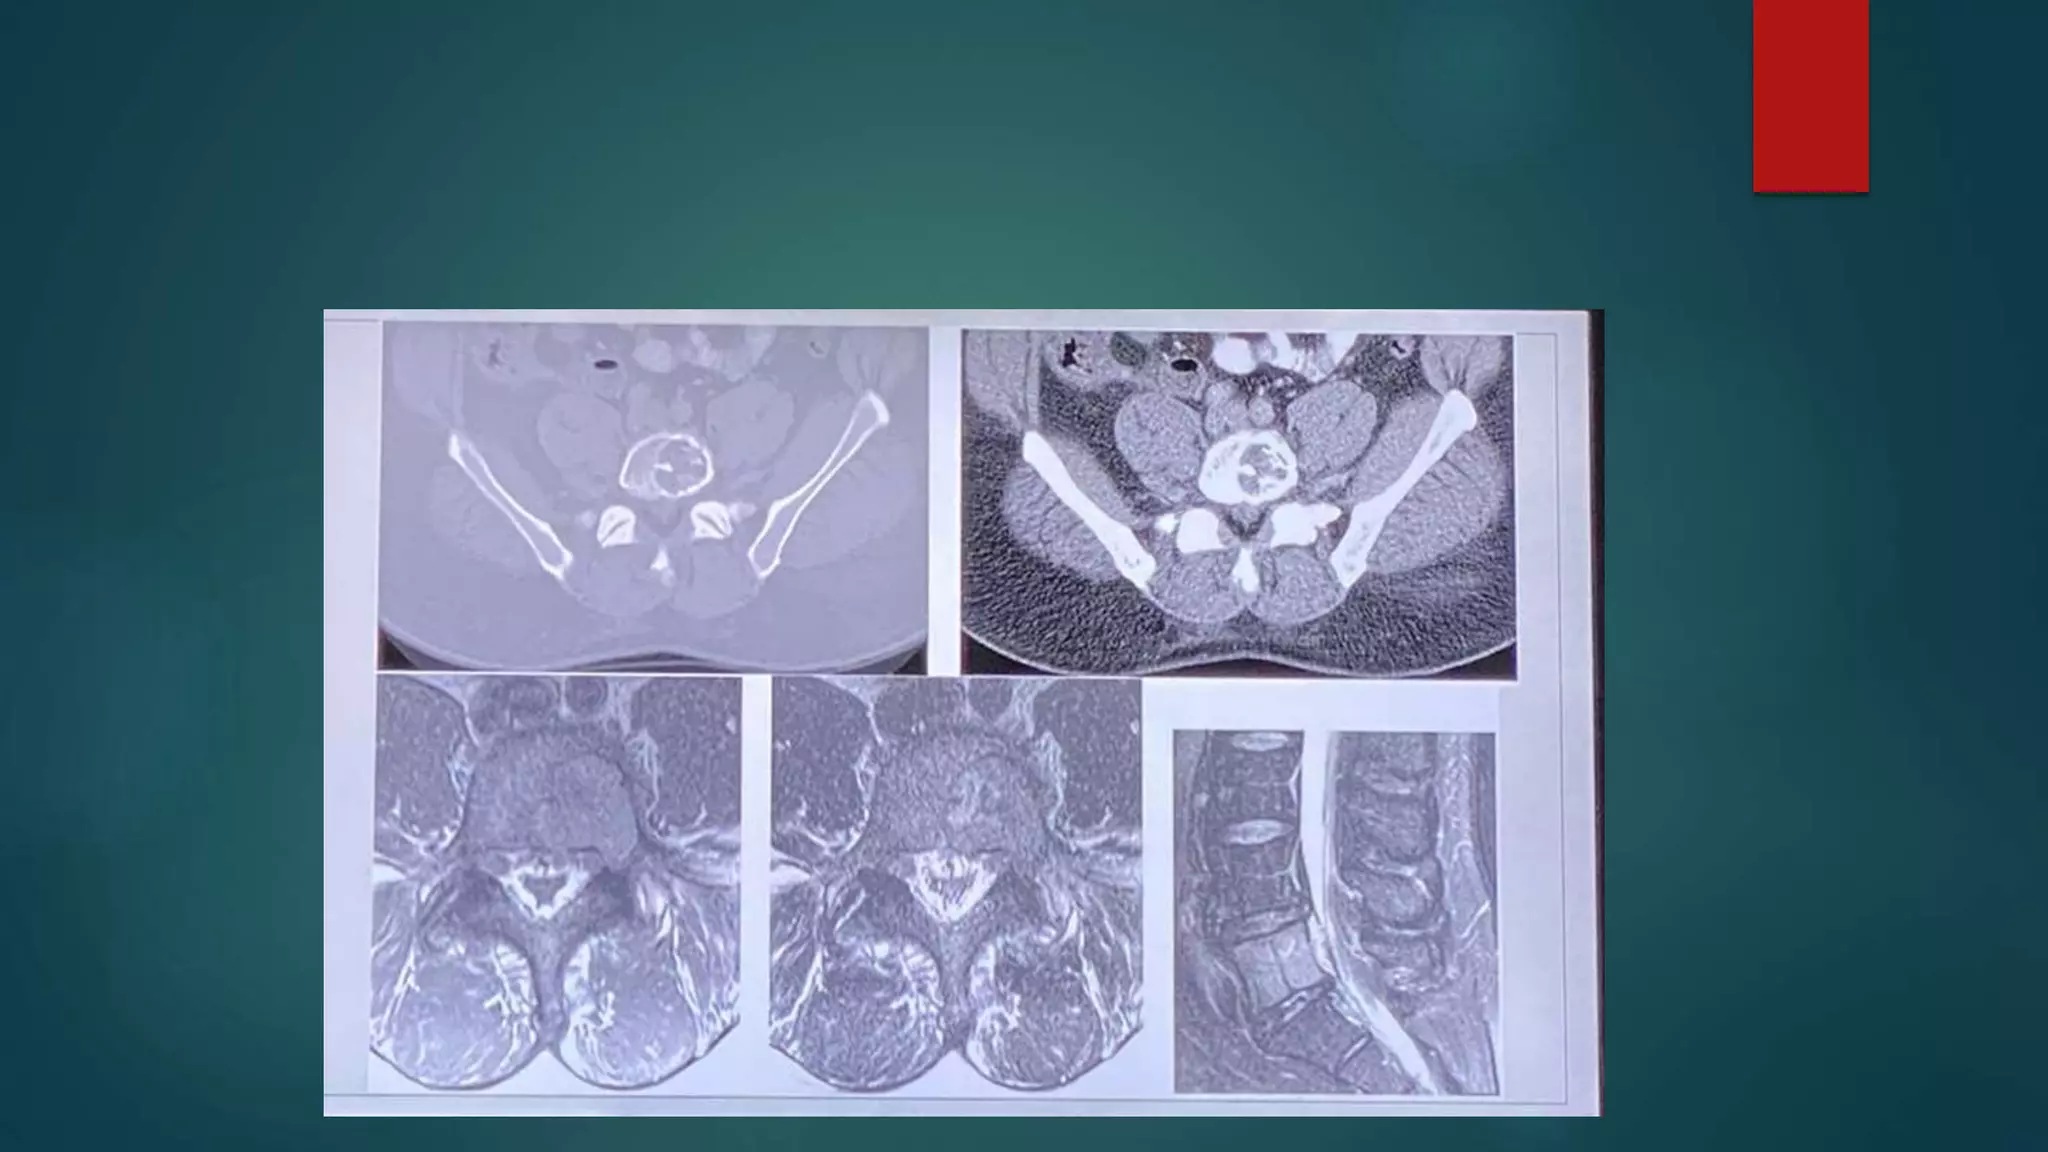

Renal important spotter

Megaureter

Ectopic kidney and pancake kidney

Horseshoe kidney

• #38 Pancake kidney (also known as discoid kidney, disc kidney, lump kidney, fused pelvic kidney or cake kidney) is a rare renal fusion anomaly of the kidneys of the crossed fused variety.